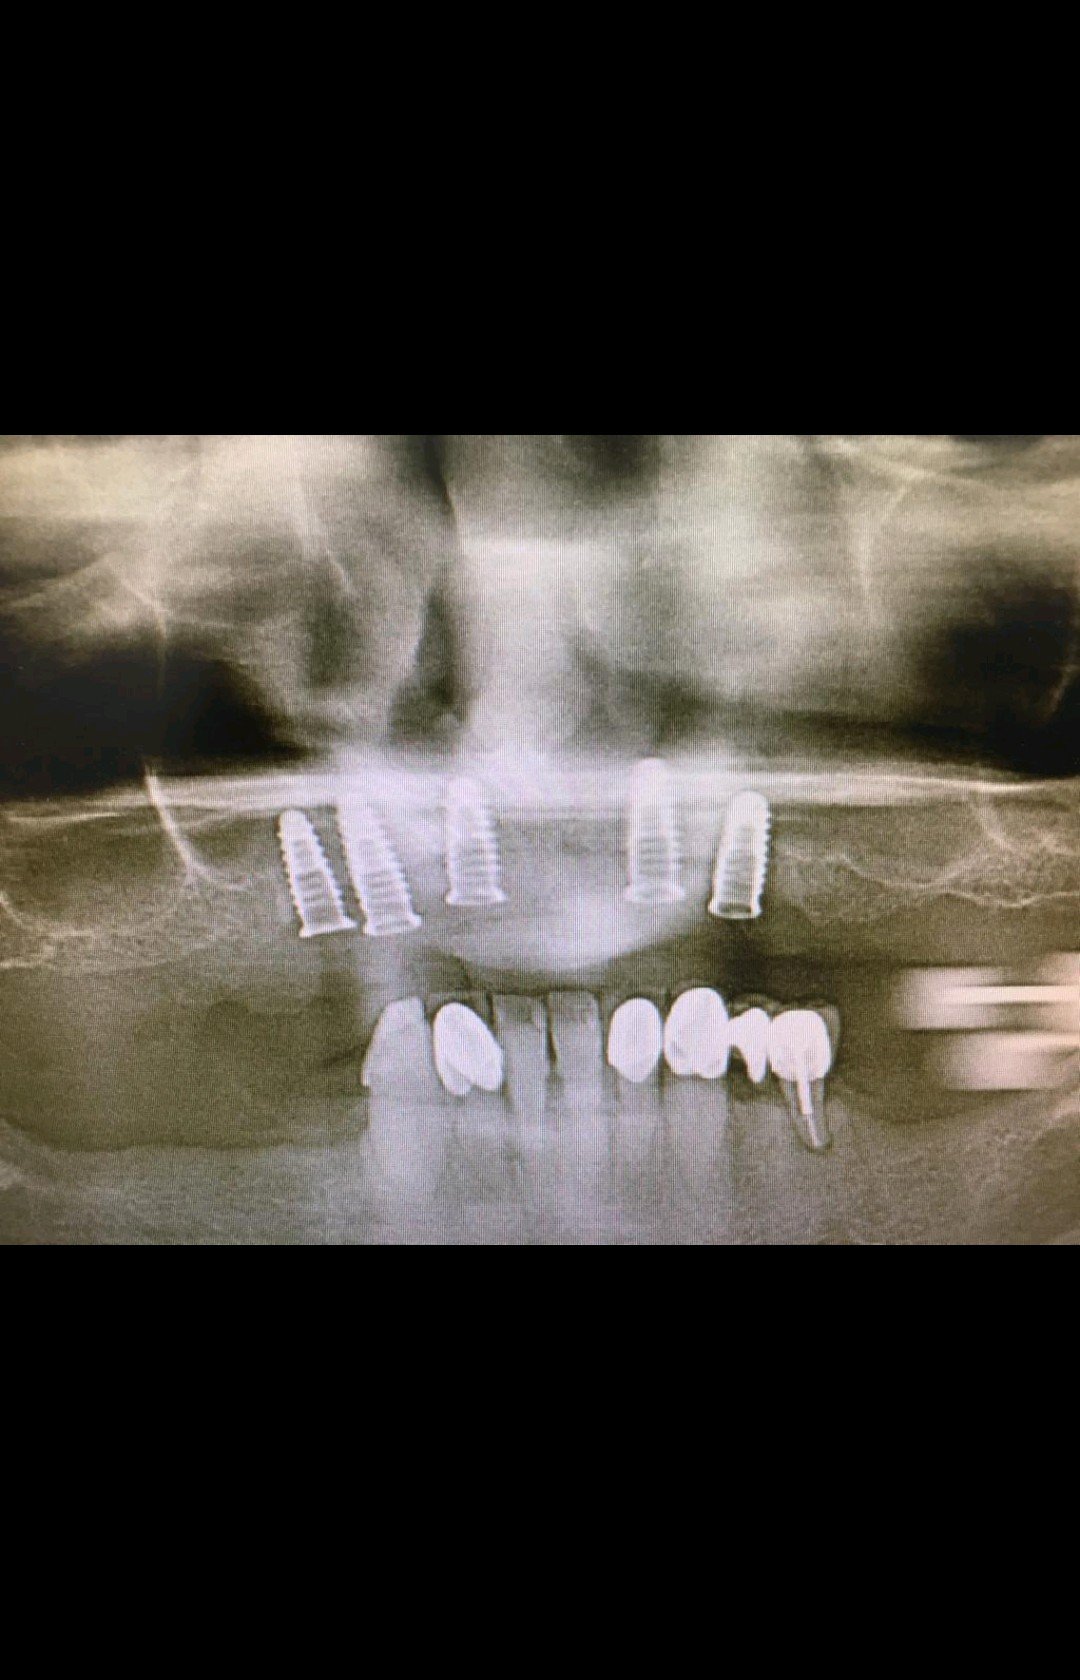

Buenas noches colegas!! Me podriaip ayudar con este caso? Necesitaría saber que implantes lleva esta paciente. Gracias!!

BUENAS TARDES, VAMOS A CAMBIAR LAS CORONAS DE ESTA PACIENTE Y ELLA NO SABE QUE IMPLANTES LLEVA COLOCADOS.